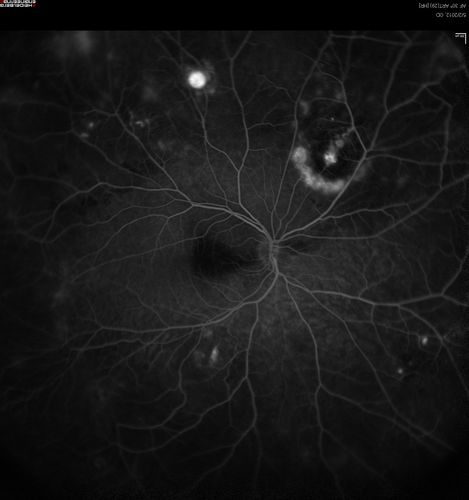

wide angle fa late. od

leaking vessels

Coats disease

saunders/pavan/usf eye institute